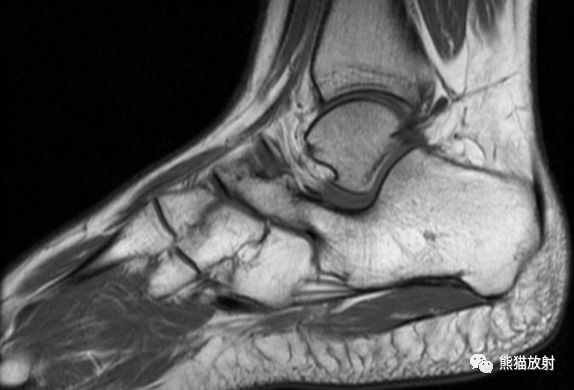

先看一个病例:患者,男性,16岁,足部疼痛。

MR矢状PD压脂、矢状T1WI;主要表现:跟骨和舟骨之间可见骨性联合,MR上相应区域无水肿

食蚁兽鼻征

1、足侧位X线片上。

2、食蚁兽的鼻子:跟骨的前上部管状伸长,接近舟骨或与其重叠。

3、提示跟舟联合

跟舟联合在侧位X线片上呈现食蚁兽鼻征,拍摄45°内斜位X片观察跟舟联合